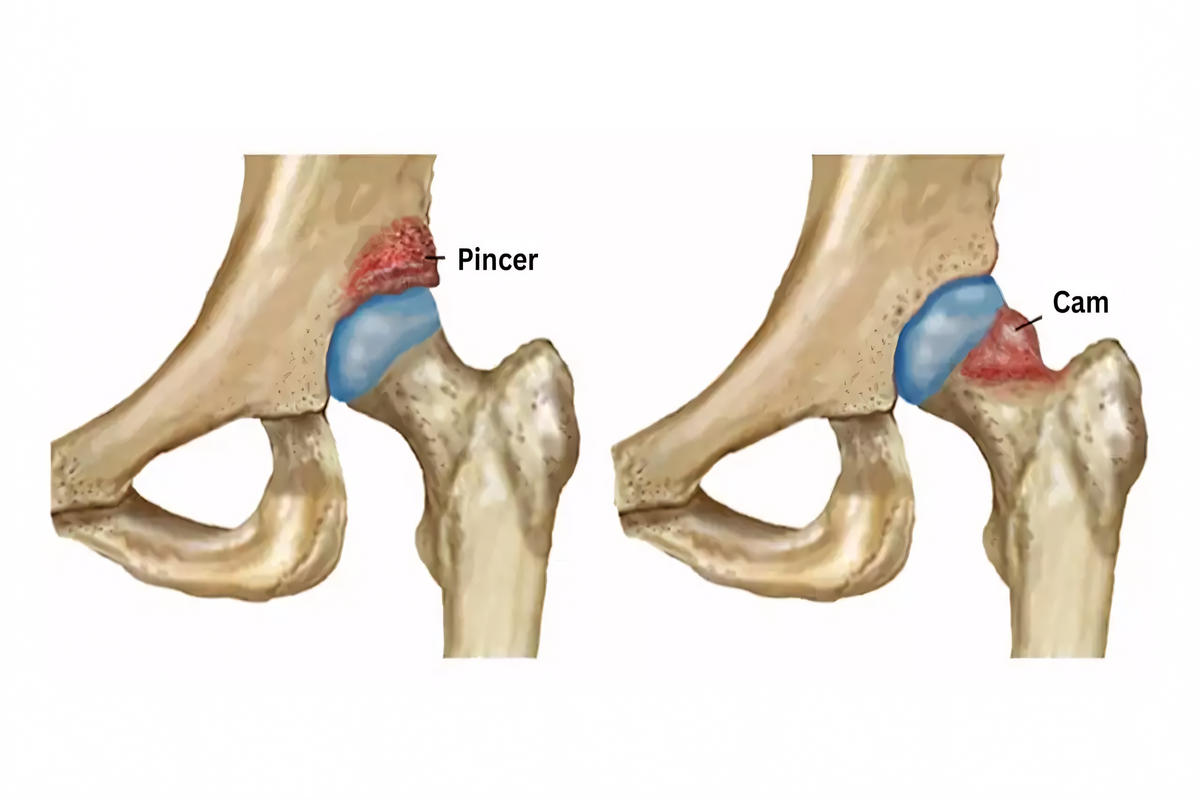

Το σύνδρομο FAI διακρίνεται σε τρεις βασικούς τύπους:

Cam τύπου

Παρατηρείται ανωμαλία στη μετάβαση κεφαλής–αυχένα μηριαίου. Η απώλεια της φυσιολογικής σφαιρικότητας προκαλεί μη φυσιολογική τριβή κατά την κάμψη και έσω στροφή του ισχίου.

Pincer τύπου

Χαρακτηρίζεται από υπερκάλυψη της κοτύλης, η οποία προκαλεί αυξημένη πίεση στον επιχείλιο χόνδρο και πρόωρη φθορά.

Μικτός τύπος

Συνδυασμός Cam και Pincer τύπου, ο συχνότερος στην κλινική πράξη.